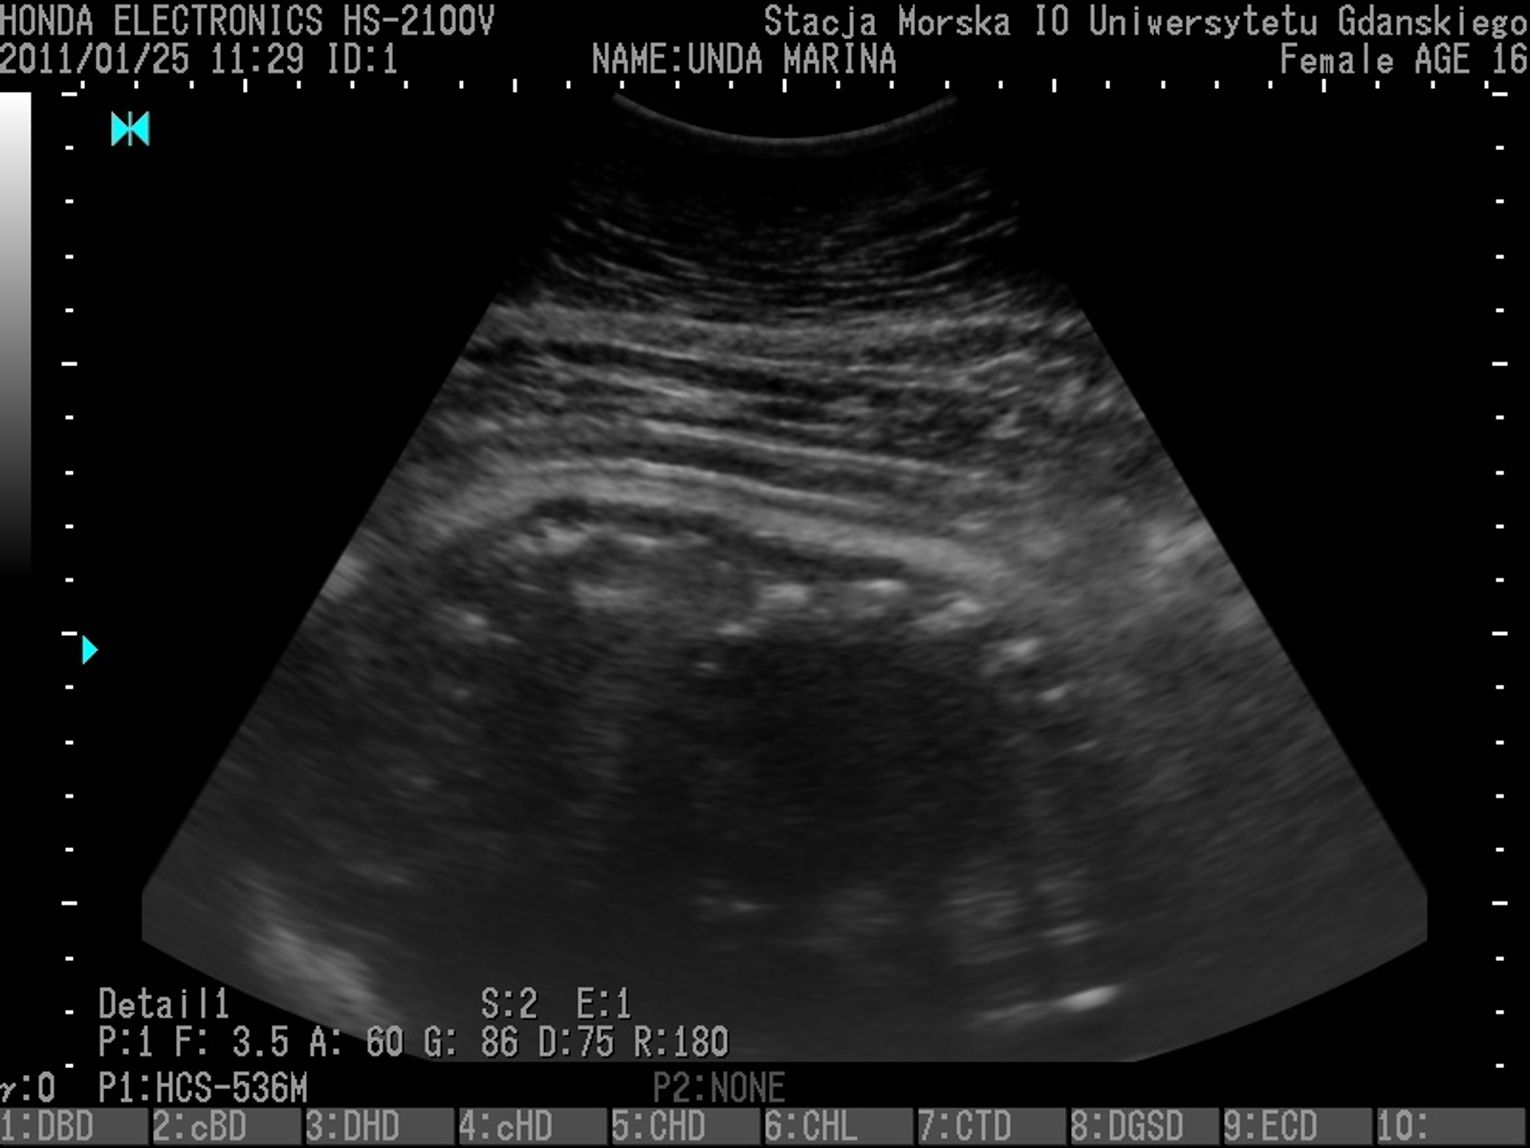

Foka Koga z USG już na świecie

GDAŃSK. W lutym, dzięki sprzętowi USG zakupionemu w ramach projektu prowadzonego przez WWF, widzieliśmy ją jeszcze w łonie matki. Dziś przyszła na świat. Mała foka o imieniu Koga jest drugą, urodzoną w tym roku w helskim fokarium. Jej matką jest Unda Marina.